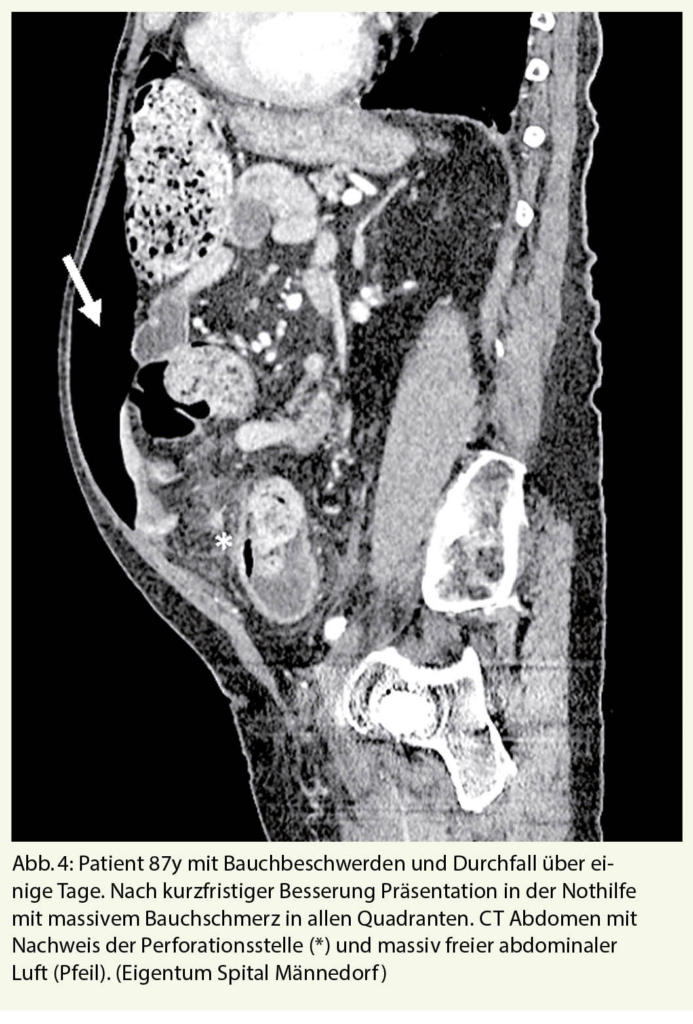

Akute Divertikulitis

Die akute Divertikulitis des Dickdarms ist eine der häufigsten Erkrankungen, die zu einer Einweisung in den Notfall führen. Bei mehr als 50 % der über 65-Jährigen liegt eine Divertikulose vor, aus der in 10-25% eine akute Divertikulitis entstehen kann (13, 14). Auch bei einer perforierten Divertikulitis können typische Schmerzen im linken Unterbauch mit Abwehrspannung fehlen, so dass auch hier nur eine Computertomographie des Abdomens zur Klärung der Situation beiträgt. Nicht selten präsentieren sich ältere, immungeschwächte Patienten primär mit einer frei perforierten Sigmadivertikulitis, die mit einer massiven eitrigen Peritonitis und entsprechend hoher perioperativer Letalität einhergehen kann (Abb. 4)